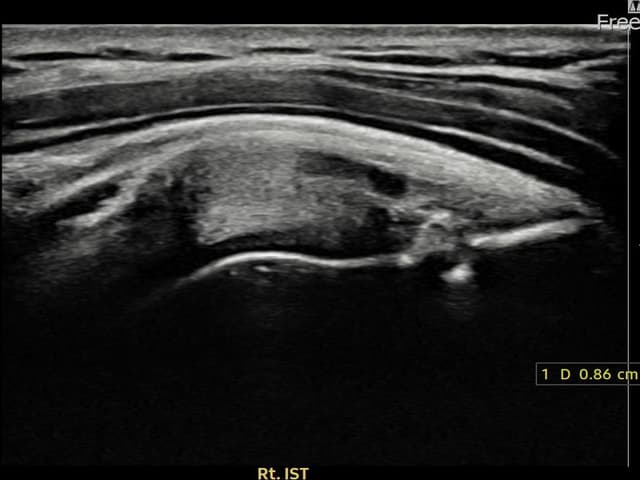

[촬영시기:23.12.14~24.02.22]

[어깨인대 축소봉합술] 우측 어깨 후방 통증과 외회전 시 심한 통증으로 내원하셨습니다.